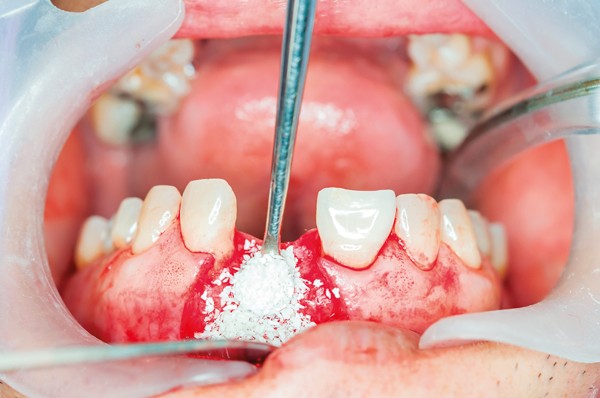

Socket preservation is a bone grafting procedure performed immediately after a tooth extraction to help maintain the natural shape and volume of the bone and gum tissue. When a tooth is removed, the surrounding bone can begin to deteriorate quickly, affecting future options for dental implants or bridges. This technique helps protect the site and prepare it for future restoration.

After the tooth is gently removed, the empty socket is carefully cleaned and filled with a bone grafting material. This material may come from the patient’s own body, a donor source, or synthetic alternatives. Once in place, the graft is typically covered with a protective membrane and sutured to secure the area.